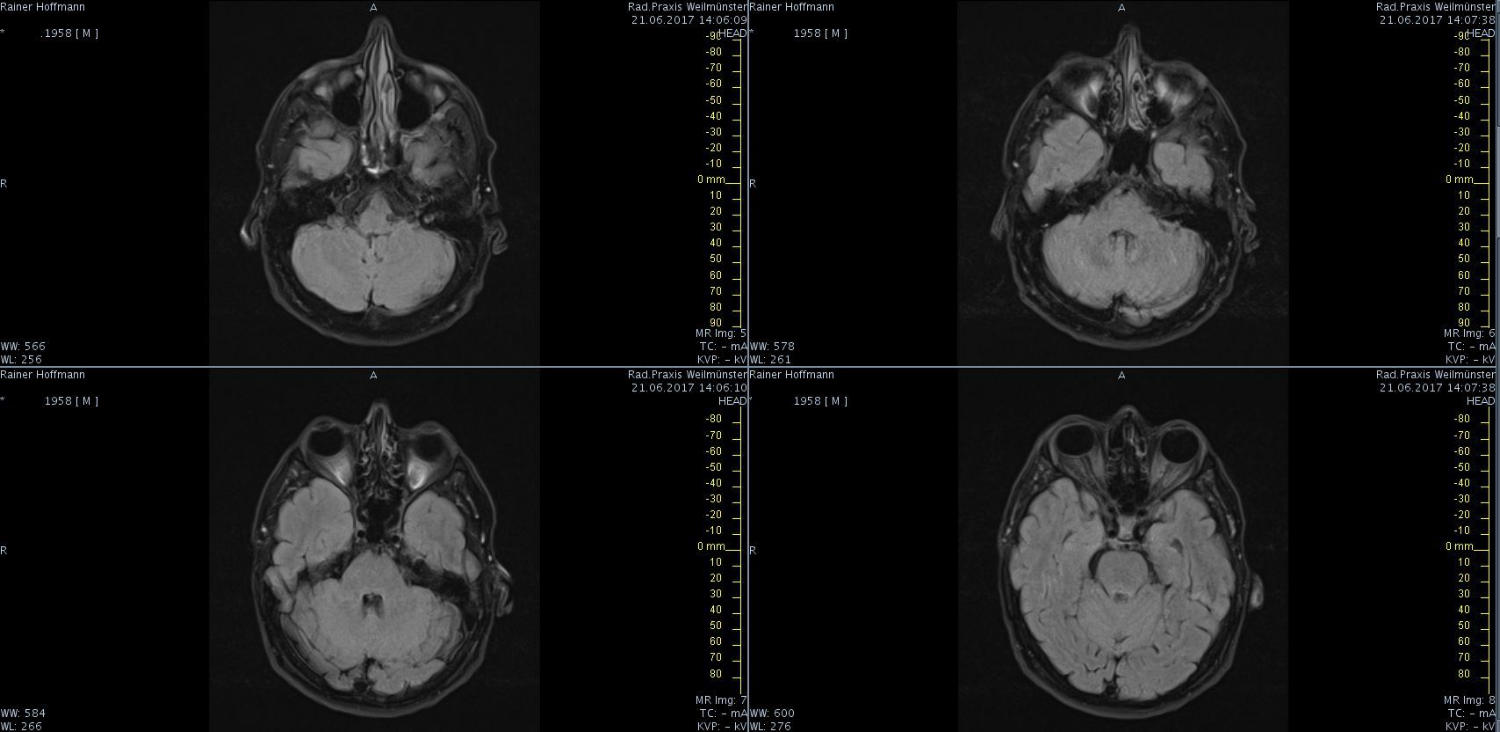

Das ist ja ganz toll, dass Ihr die Seite so schnell gefunden habt. Ich zeige euch jetzt ein ganz, ganz anderes Paßfoto von mir. Es könnte Ähnlichkeiten zu anderen lebenden oder bereits verstorbenen Personen geben. Wenn Ihr das erste Bild oben links anklickt wird es ver- größert dargestellt. Dann kann man mit den Pfeiltasten am unteren Bild- rand durch meinen Kopf blättern. Es gibt nicht viel zu sehen. Vielen Dank an Martina für Ihre Hilfe.

MRT